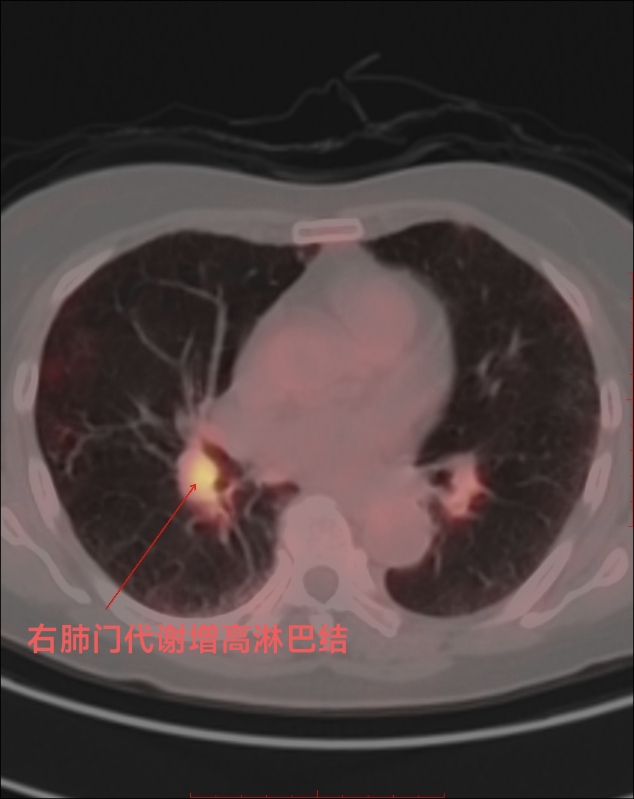

70多岁的詹先生因发热、腹泻就诊于潞河医院,抗感染治疗效果不佳,进行了支气管镜检查提示右肺中叶外侧段支气管闭塞,完善CT检查提示双侧肾上腺体积增大并异常强化。这些结果都指向了一个可怕的诊断—肺癌、肾上腺转移、淋巴结转移。为了评估全身情况,制定进一步的诊疗计划,临床医师建议詹先生进行PET/CT检查。詹先生做完PET/CT检查后,核医学科主任郑立春主持科内集体阅片:检查结果并没有发现明确的肺癌病灶,而右肺门淋巴结肿大、代谢增高,压迫了右肺中叶部分支气管,才是导致相应支气管闭塞的罪魁祸首。此外,腹盆部小到0.5cm,大到1.2cm的淋巴结均显示出较高的代谢,高度提示为恶性病变。双侧肾上腺体积异常增大、代谢显著增高,提示恶性病变,但是不太符合转移瘤的代谢表现。此次检查还意外发现詹先生的小肠有多处代谢增高,部分肠管管壁稍增厚,但是肠管管腔并不狭窄,反而呈扩张的状态。经过认真分析综合考虑,詹先生得的并不是肺癌、肾上腺转移、淋巴结转移,而是淋巴瘤多脏器累及(小肠、肾上腺、淋巴结)。随后,詹先生来到血液科进行了肾上腺穿刺活检后证实为弥漫大B细胞淋巴瘤,并制定了详细的治疗计划。PET/CT检查为临床医生拨开了迷雾,在疾病诊断的道路上找到正确的方向,大大节约了詹先生的就医时间和经济成本,使他能够获得及时、有效的治疗。